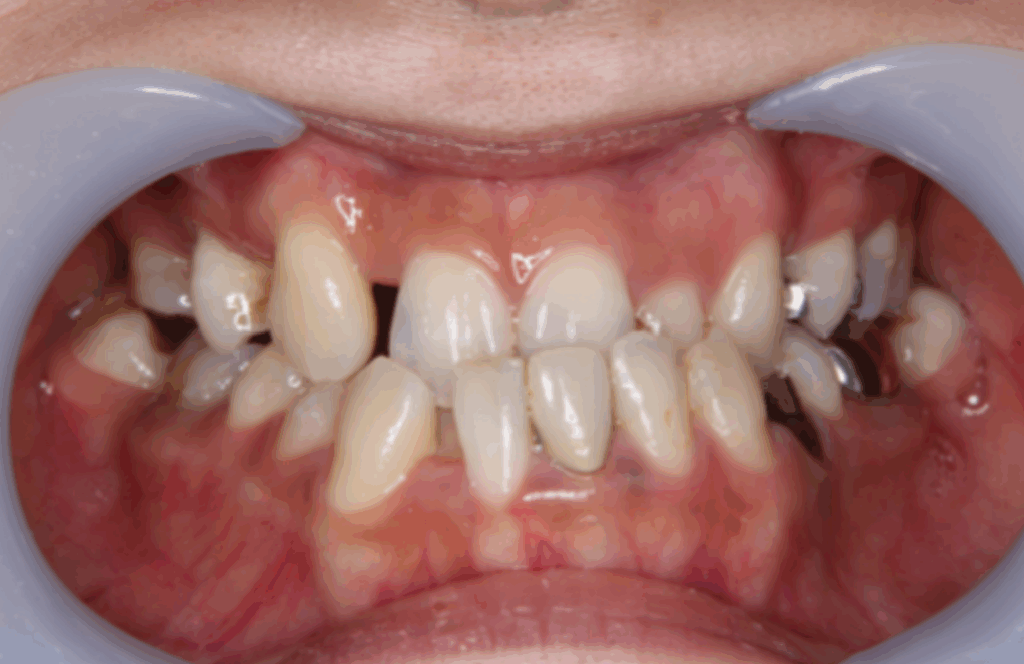

■ 現代は「歯並びの乱れ」が増えている時代です

近年、お子様の歯並びが悪くなるケースが急増しています。

これは、現代の食生活で柔らかい食べ物が増え、

顎が十分に成長しないまま永久歯が生えるため といわれています。

■ 歯並びが悪いことで起こる問題

歯並びの乱れは、見た目だけの問題ではありません。

● 歯垢が溜まりやすい

● むし歯・歯周病のリスクが高まる

● 発音がしづらい

● かみ合わせの不調和

● 頬や舌を噛みやすい

● 口元を気にして笑えない・隠してしまう

このように、機能面・健康面・メンタル面 にも影響し、

日常生活にストレスを抱える原因になることもあります。